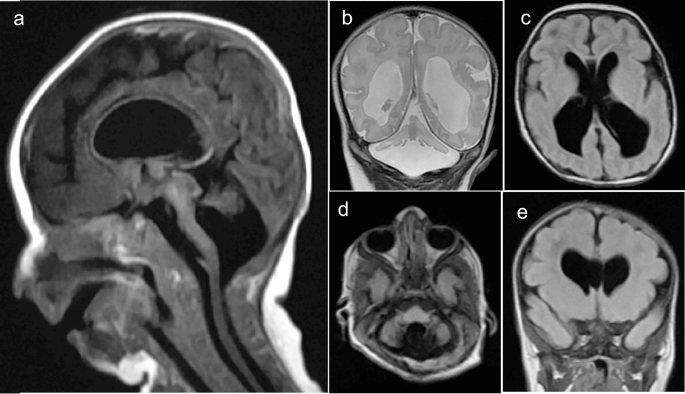

Magnetic resonance imaging (MRI)

Brain MRI revealed a marked hypoplastic cerebellum with a small remnant of vermis, hypoplastic pons, lateral ventriculomegaly (third and fourth), and a dilated cerebellar-medullary cistern (Fig. 2). However, the posterior fossa and the visualized parts of the orbits and peripheral nervous system are within normal limits. Based on the brain MRI, the affected individuals were initially diagnosed as having pontocerebellar hypoplasia (PCH).